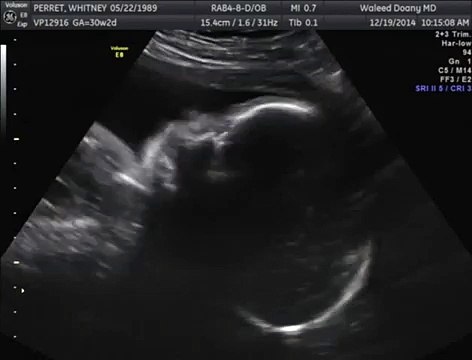

Baby Yawns in Womb - 4D Ultrasound Video Footage